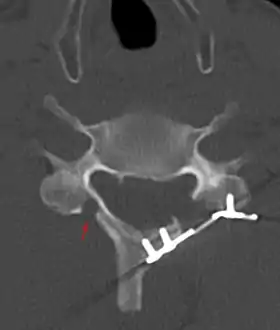

CT scan of Laminoplasty of cervical vertebra